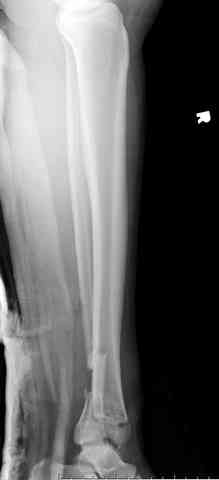

Дополнительные ренгенограммы после дистракции и

обязательная комьютерная томография дают возможности разузнать топографию расположения фрагментов, что немаловажно для планирования хирургического доступа.

По апексу фрагмента ориентируется при планировании

фиксации, также предоперационно определяется

направление фиксирующего материала: шурупа или спицы с упорной площадкой.

Первичная пластина или интрамедуллярный фиксатор на малоберцовую зависит от характера перелома, косые и многооскольчатые пластинами, а поперечных можно интрамедуллярными фиксаторами. Восстановленная длина малоберцовой служит ориентиром и помогает определению высоты большеберцовой во время восстановления.

Здесь выставлена пара случаев перелома пилона, оба

случая леченные этапным наружным фиксатором.